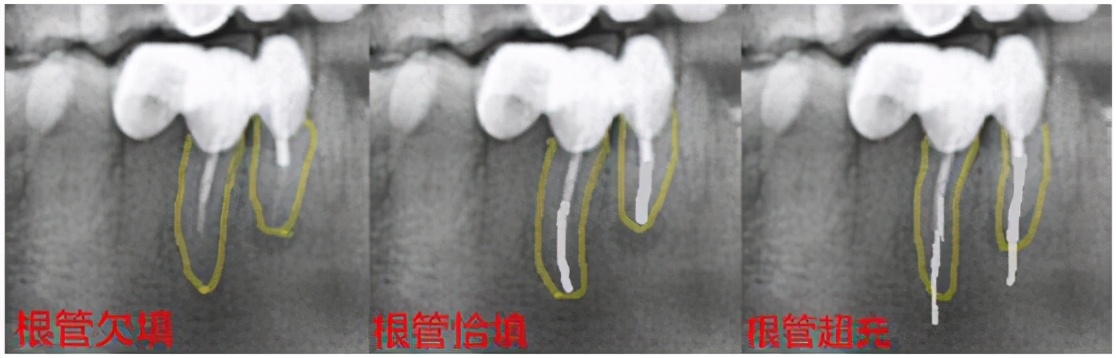

根管治疗遇到髓室底底穿,根管壁侧穿,根管充填欠填、超填,遗漏根管,断针,根管折断……等情况均可能导致根管治疗的失败。

(黄色线为牙根,白色线为根充物)

所有的治疗,都没有百分之一百的成功率,随着牙体牙髓学理论的进步,技术的发展,根管治疗的远期成功率,也只能无限的接近百分之一百。

因此,即便我们在根管治疗时,出现上述情况,也别太过于害怕,请相信你的牙医,他们会尽力避免上述情况的出现,一旦出现上述情况,仍有一定的补救手段可以使用。